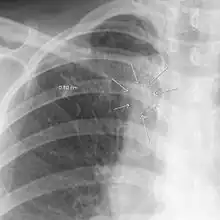

| The arrows denote an ill-defined nodular opacity in medial aspect of right upper lobe with ill-defined rim of lucency surrounding it | |

| Differential diagnosis | Aspergilloma |